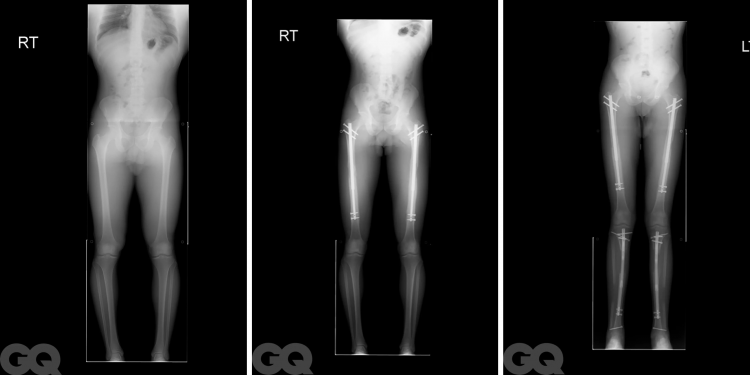

John'un ayakta olması etkileyici - ve muhtemelen aptalca - özellikle de sadece birkaç ay önce boyunun 173 cm olduğu düşünülünce. Eylül ayında, bacaklarını ameliyatla uzatmak için 75.000 dolar ödemiş.Bu, hem uyluk kemiğinin kırılmasını hem de merkezlerine ayarlanabilir metal çivilerin takılmasını gerektiriyor. Her çivi, kemik gibi hem esnek hem de sağlam olan ve yaklaşık bir pikolon boyutundaki titanyumdan yapılıyor. Çiviler manyetik uzaktan kumanda ile yaklaşık 90 gün boyunca her gün bir milimetre uzatılmış. Kırık kemikler iyileştiğinde, işte karşınızda daha yeni, daha uzun bir John.

Çivi nihayet artık kopmuş kemiğe yerleştirildiğinde, Dr. D bacak boyunca birkaç küçük kesik daha atıyor ve her şeyi bir arada tutmak için birkaç vida ekliyor. Röntgen ekranında hastanın uyluğu rüzgar gülü gibi görünüyor.

Dr. D'nin açıkladığı gibi, John'un femurları tam olarak konsolide olmuş durumda değil. Sol tarafı yüzde 95 iyileşmiş ancak sağ tarafı sadece yüzde 80 iyileşmiş durumda. Yani kemik dokusu hala şekilleniyor, hala esnek ve biraz yumuşak. Çivi herhangi bir düşüşte hasar görürse, yenisiyle değiştirmek zorunda kalacaklar ve tüm süreç yeniden başlayacak. (Bu, şu ana kadar sadece birkaç kez olmuş.)